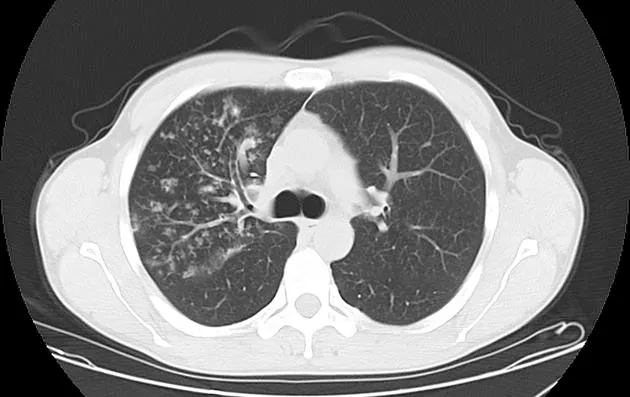

Post-primary pulmonary tuberculosis

대부분의 환자는 다음 두 곳에 생김

Posterior segments of the upper lobe

superior segments of the lower lobe

Typical findnigs

1) Patcy consolidation 또는 poorly defined linear and nodular opacities